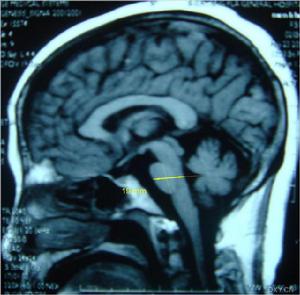

(4)輔助檢查:①X片可見脊柱和骨骼畸形;MRI可見脊髓變細;②心電圖常見T波倒置、心律失常和傳導阻滯,超聲心動圖示心室肥大,視覺誘發電位波幅下降;③DNA分析FRDA基因18號內含子GAA大於66次重複。

遺傳性共濟失調2、Friedreich型共濟失調(FRDA)X片可見脊柱和骨骼畸形;MRI可見脊髓變細;心電圖常見T波倒置、心律失常和傳導阻滯,超聲心動圖示心室肥大,視覺誘發電位波幅下降。